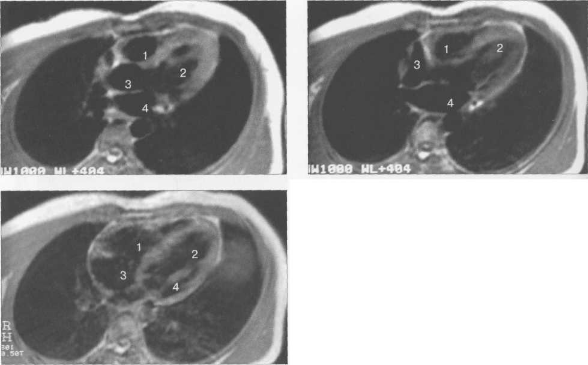

б) Вопросы лучевой диагностики. Селезенка имеет уникальную тканевую структуру и состоит из красной и белой пульпы, что обусловливает ее характерный вид при лучевых исследованиях. Белая пульпа образована лимфоидной тканью, а красная - сосудами и селезеночными тяжами (скоплениями клеток, разделенными синусоидами). В связи с большим количеством кровеносных сосудов красная пульпа быстро накапливает контраст, из-за чего структура селезенки становится неоднородной в артериальную фазу КТ- либо МР-исследования. Эту особенность можно ошибочно принять за патологические изменения, однако данный феномен не определяется при исследованиях без контрастного усиления либо в отсроченную фазу.

КТ является методом выбора для оценки изменений со стороны селезенки при острых состояниях (травме, выраженной болевой симптоматике). Для оценки объемных образований селезенки и при некоторых метаболических заболеваниях (например, гемохроматозе) дополнительно может использоваться МРТ. Селезенка характеризуется относительно длинным временем релаксации Т1 и Т2, вследствие чего выглядит гипоинтенсивной по отношению к паренхиме печени на Т1 ВИ и гиперинтенсивной на Т2 ВИ. При накоплении в ткани селезенки железа интенсивность сигнала от нее может в значительной степени снижаться.

(Слева) На аксиальной КТ в артериальную фазу контрастного усиления определяется выраженная неоднородность структуры селезенки в результате быстрого накопления контраста в сосудистых синусоидах (красной пульпе), что не должно ошибочно приниматься за патологический процесс.

(Слева) На аксиальной КТ с контрастом в венозную фазу селезенка выглядит однородной. (Слева) На аксиальной Т1 ВИ МР томограмме (А) визуализируется неизмененная селезенка, несколько гипоинтенсивная по отношению к паренхиме печени. На Т2 ВИ МР томограмме (В) сигнал от селезенки в норме слегка более интенсивен, чем от печени.